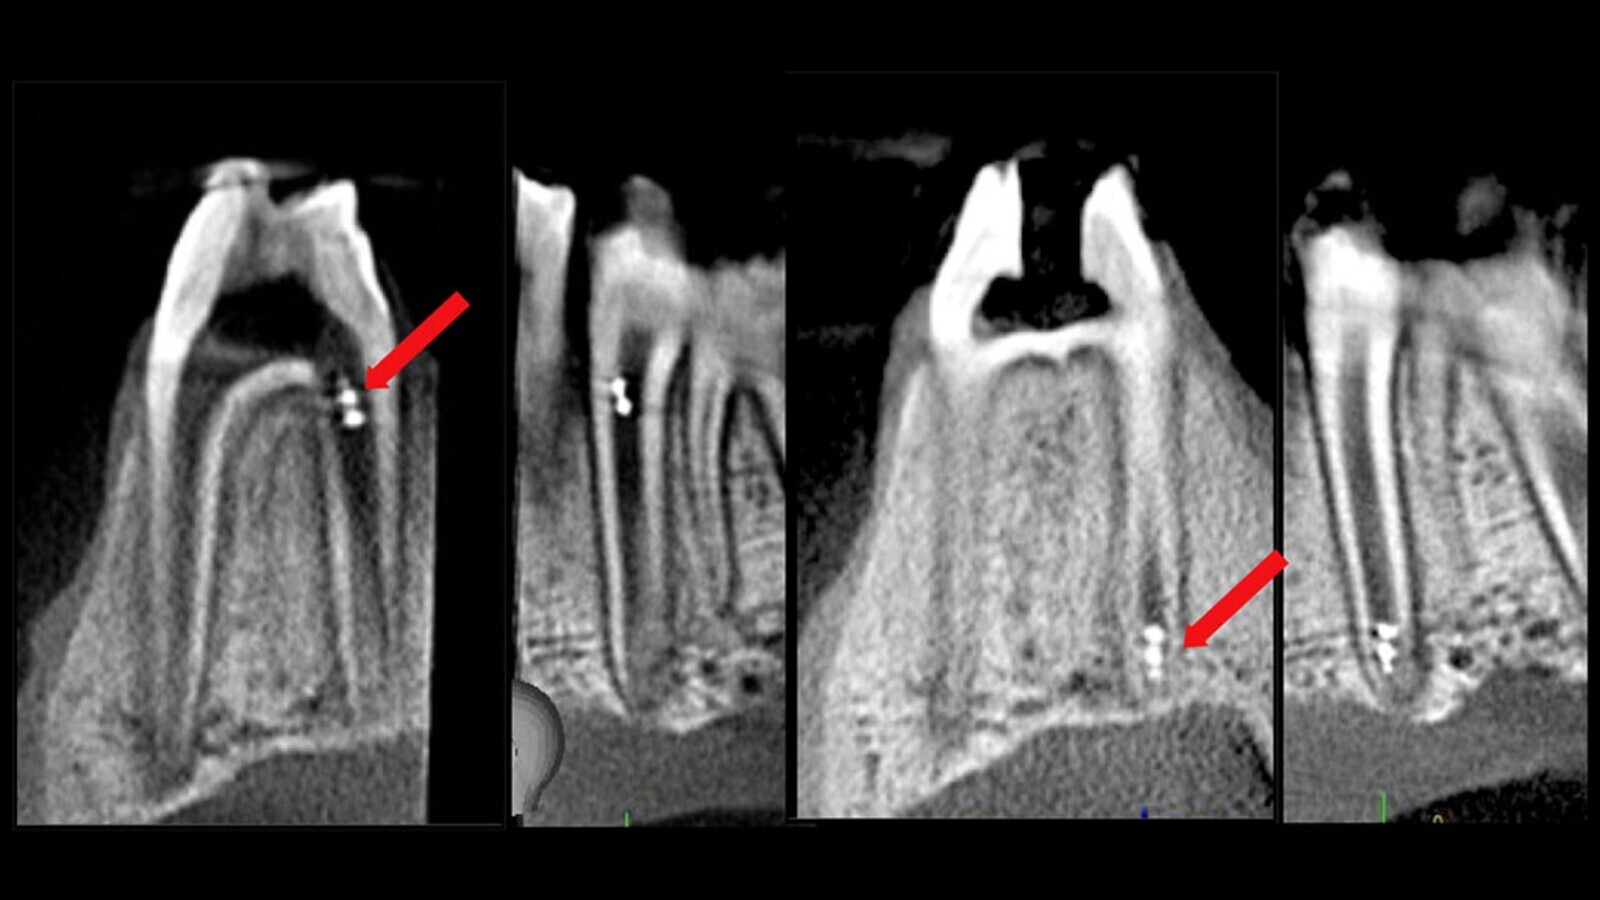

„Нашите открития доказват, че благодарение на многофункционалността на микророботите е възможно да бъдат третирани труднодостъпни зони от ендодонциума, да бъде унищожен биофилмът и да се вземат проби за микробиологичен анализ в реално време. Освен това демонстрирахме, че е приложимо проследяването на роботите вътре в кореновия канал, използвайки съвременни клинични образни методи“, допълва той.

Магнитно задвижвани 3D-принтирани роботи биват прецизно контролирани, така че невъзпрепятствано от заобикалящия периодонциум да достигнат до апикалната една трета на кореновия канал, както е визуализирано и проследено на CBCT. (Снимка: Университетът на Пенсилвания)